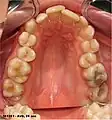

La section buccale part de l'apex de la langue jusqu'au sillon terminal et est parcourue par un sillon médian. C'est sur cette partie que se trouvent les papilles.

Papilles gustatives

Chez l'humain, les papilles gustatives permettent de reconnaître les différentes saveurs : sucré, salé, amer, l'umami et l'acide. Des papilles gustatives recouvrent la langue et sont responsables de la perception des goûts. Les papilles se classent en quatre sortes :

- les papilles circumvallées (ou caliciformes), au nombre de 12, formant le V lingual qui délimite les 2/3 antérieur du 1/3 postérieur de la langue ;

- les papilles fongiformes, disséminées sur la pointe et les 2/3 antérieur de la langue ;

- les papilles filiformes, celles qui sont présentes en plus grand nombre et donnent à la langue sa texture particulière et situées de part et d'autre du sillon médian ;

- les papilles foliées (ou coralliformes), situées sur les bords latéraux et postérieurs de la langue.